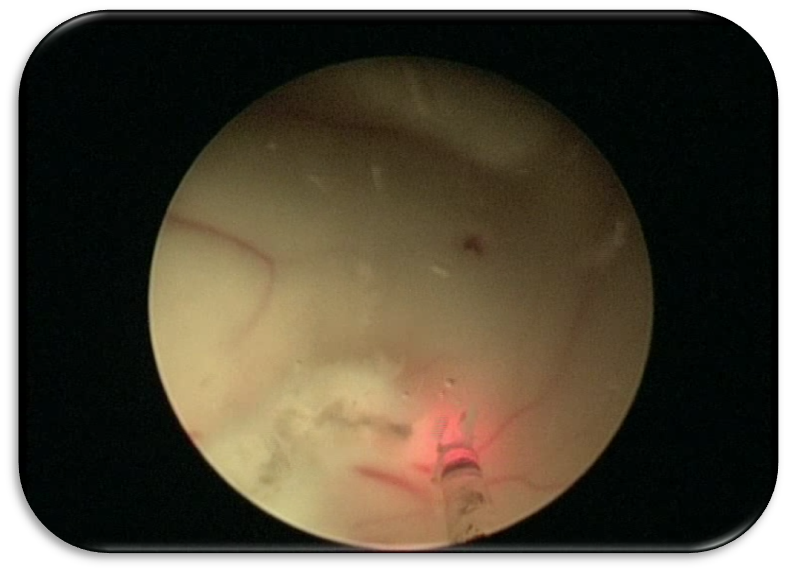

【鞍结节脑膜瘤(包裹视神经、颈前动脉)、肿瘤边界分离】

激光辅助脑室镜三脑室底造瘘术(ETV)通过多个穿孔建立脑脊液引流通道,治疗梗阻性脑积水。